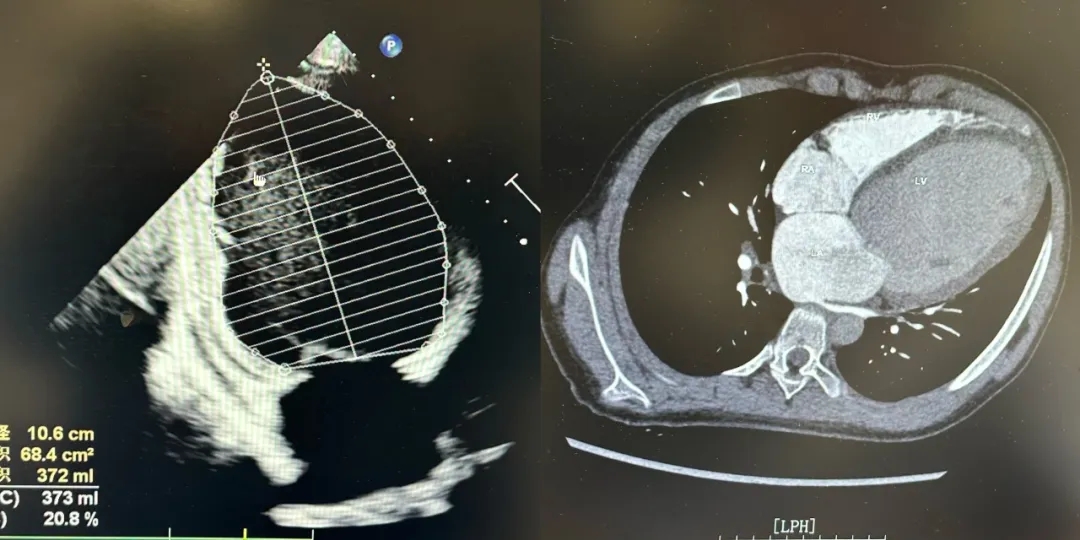

检查结果令人揪心:先天性心脏病、主动脉瓣重度关闭不全、主动脉瓣大量反流、左室射血分数(EF值)仅21%,而正常人的范围是50%-70%。“先心病患儿本身就容易因感冒诱发心衰,这孩子入院时,心脏像一个过度充气后失去弹性的气球,属于典型的终末期心衰,情况非常危急。”医大医院心脏大血管外科学科带头人万峰教授回忆道。